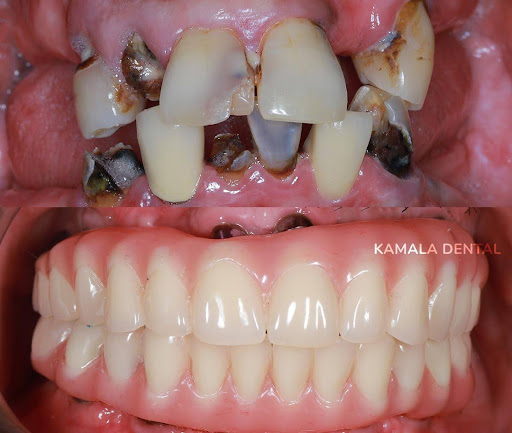

Full Mouth Rehabilitation – Comprehensive Care

This multidisciplinary approach combines different corrective procedures for damaged teeth. Full mouth rehabilitation restores both function and aesthetics, giving patients a complete smile makeover while ensuring long-term oral health.